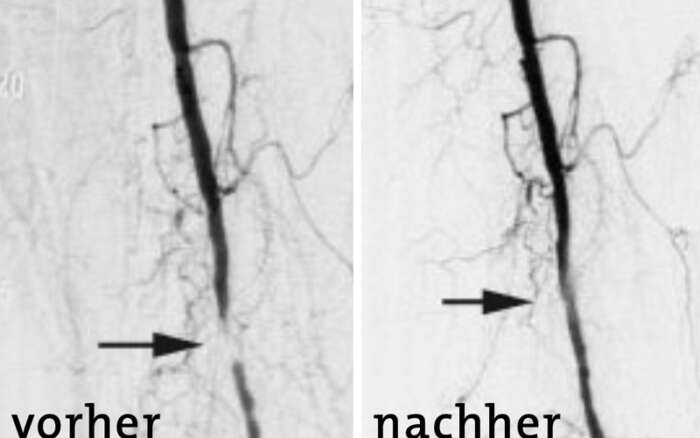

Hierfür wird ein sehr dünner Katheter («Schlauch») unter Röntgenkontrolle in das erkrankte Blutgefäss eingebracht. Über diesen Katheter wird anschliessend Kontrastmittel verabreicht und dadurch das Blutgefäss auf dem Durch-leuchtungsbild erkennbar. So lassen sich krankhafte Gefässeinengungen oder Gefässerweiterungen gut darstellen und auf dem gleichen Weg über den liegenden Katheter meist auch gleich behandeln.

Diese Technik und die verwendeten Materialien sind heutzutage so weit entwickelt, dass auch kleine Blutgefässe im Becken und den Beinen gut erreicht und behandelt werden können.